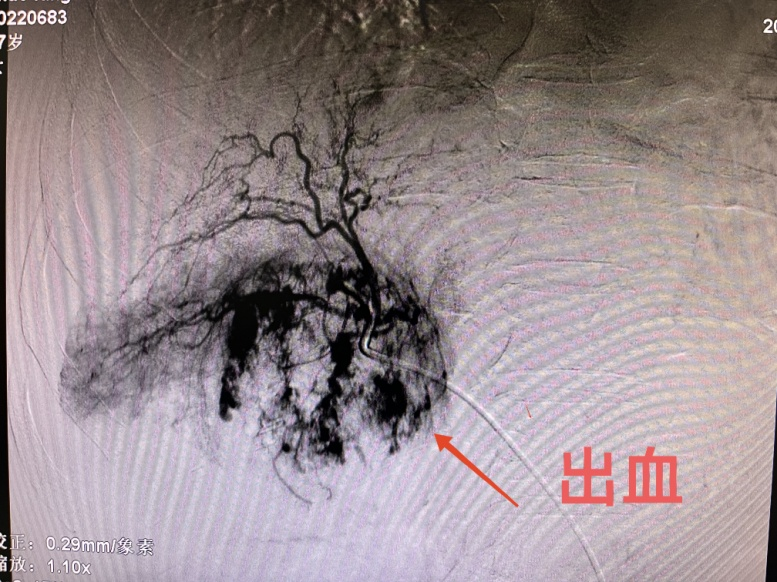

患者女性,57岁,3月12日,突发腹部疼痛就诊于当地医院,CT示肝肿瘤破裂出血,随即转入市中心医院急诊科,分诊后入住普外科二病区。急查实验室检查示:血红蛋白71g/L,血压85/60mmHg左右,正值周日,值班人员电话紧急请介入科会诊,经分析,患者随时有失血性休克风险,当即立断启动疫情状态下的急危重症患者介入诊疗绿色通道。应急值班人员第一时间到位,行肝动脉造影明确了出血动脉(部位),现场评估并制定了手术方案,对肿瘤出血进行了封堵及TACE,术后给予止血、保肝、输血、抗感染等对症处理,病情稳步好转。复查CT肝内碘油沉积良好(提示介入治疗疗效佳),目前已安全出院。